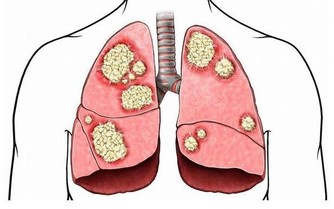

俗話說,“早上吸煙,早歸西天”。晨起後立馬抽煙可能成為高血壓患者發病的助推器,因為早餐是心腦血管疾病的高發時期。

另外,美國賓夕法尼亞州立大學醫院的研究人員在研究中發現,醒來30-60分鐘吸煙的人罹患肺癌的機率是醒來1小時候再抽煙的人的1.31倍,而一覺醒來就抽煙的人則是1.79倍。